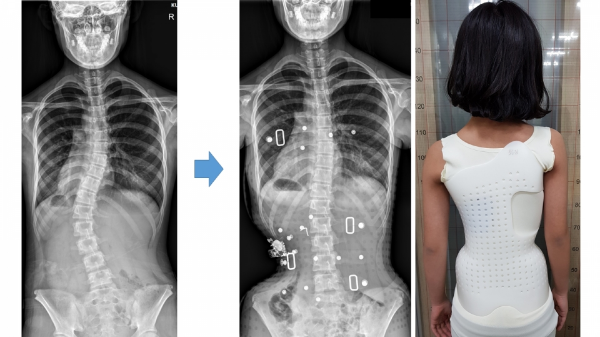

2. 보조기 착용

중등도 척추측만증이 있는 청소년의 경우 척추가 더 이상 휘어지는 것을 방지하기 위해 보조기 착용을 권장하는 경우가 많습니다. 다양한 유형의 보조기를 사용할 수 있으며, 선택은 개별 사례에 따라 다릅니다.